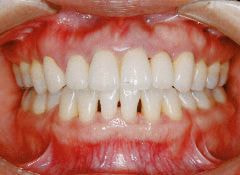

治療例2 (補綴処置+矯正)